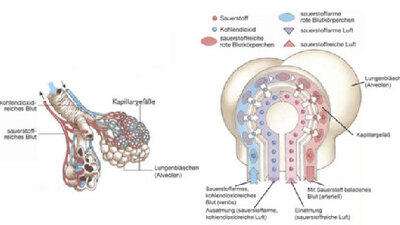

Bei einem schweren Verlauf von Covid-19 entwickelt sich bei vielen Patienten ein akutes Lungenversagen, kurz ARDS genannt (Acute Respiratory Distress Syndrome). Die Forschenden um Sander gingen in ihrer Studie der Vermutung nach, dass dabei das Lungengewebe der Patienten vernarbt, verdickt und unelastisch wird. Ganz ähnliche Vorgänge laufen bei einer bisher unheilbaren Form der Lungenvernarbung ab, der idiopathischen Lungenfibrose.

Die Wissenschaftler untersuchten zunächst das Lungengewebe verstorbener Patienten unter dem Mikroskop und fanden charakteristische Merkmale einer schweren Fibrose. „Bei fast allen Betroffenen haben wir enorme Schäden entdeckt: Die Lungenbläschen waren weitgehend zerstört, die Wände deutlich verdickt. Außerdem fanden wir ausgeprägte Ablagerungen von Kollagen, welches ein Hauptbestandteil von Narbengewebe ist“, sagte Peter Boor vom Institut für Pathologie an der RWTH Aachen.

Typischerweise entwickele sich das Lungenversagen erst zwei bis drei Wochen nach Auftreten der ersten Symptome, erläuterte Sander. „Das weist darauf hin, dass nicht die unkontrollierte Virusvermehrung zum Versagen der Lunge führt, sondern nachgeschaltete Reaktionen, beispielsweise des Immunsystems, eine Rolle spielen.“ Das Team untersuchte deshalb im nächsten Schritt die Immunzellen in Lungenspülungen und Lungengewebe von schwer erkrankten oder verstorbenen Covid-19-Patienten.

Sie fanden, dass sich vor allem Makrophagen in der Lunge betroffener Patienten ansammeln. Diese Fresszellen beseitigen normalerweise Erreger oder Zellabfälle, sind aber auch an der Wundheilung beteiligt. Bei einer schweren Covid-19-Erkrankung scheinen sie mit bestimmten Zellen des Bindegewebes in Kontakt zu treten. Diese vermehren sich daraufhin stark und bilden große Mengen des Bindegewebseiweißes Kollagen. Die Lunge vernarbt quasi. Nachfolgende Untersuchungen in Zellkulturen legten nahe, dass Sars-CoV-2 diese fehlgeleitete Reaktion der Fresszellen anstößt. Grippeviren konnten dies hingegen nicht.